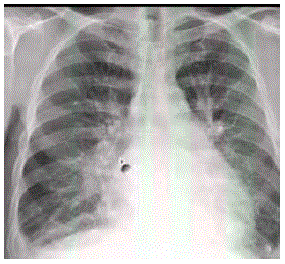

Homem, 56 anos, admitido na emergência por quadro de dispneia há 5 dias, com piora progressiva, evoluindo com tosse seca e ortopneia. Na admissão, se apresenta dispneico, com estertores em 2/3 inferiores de tórax e extremidades frias. PA: 150 x 70mmHg FC: 100. Nega febre ou expectoração. Sem histórico prévio de doença cardíaca. Não faz uso de medicações. Radiografia de tórax abaixo.

Qual a conduta inicial?

LEGENDA: PA: pressão arterial; FC: frequência cardíaca